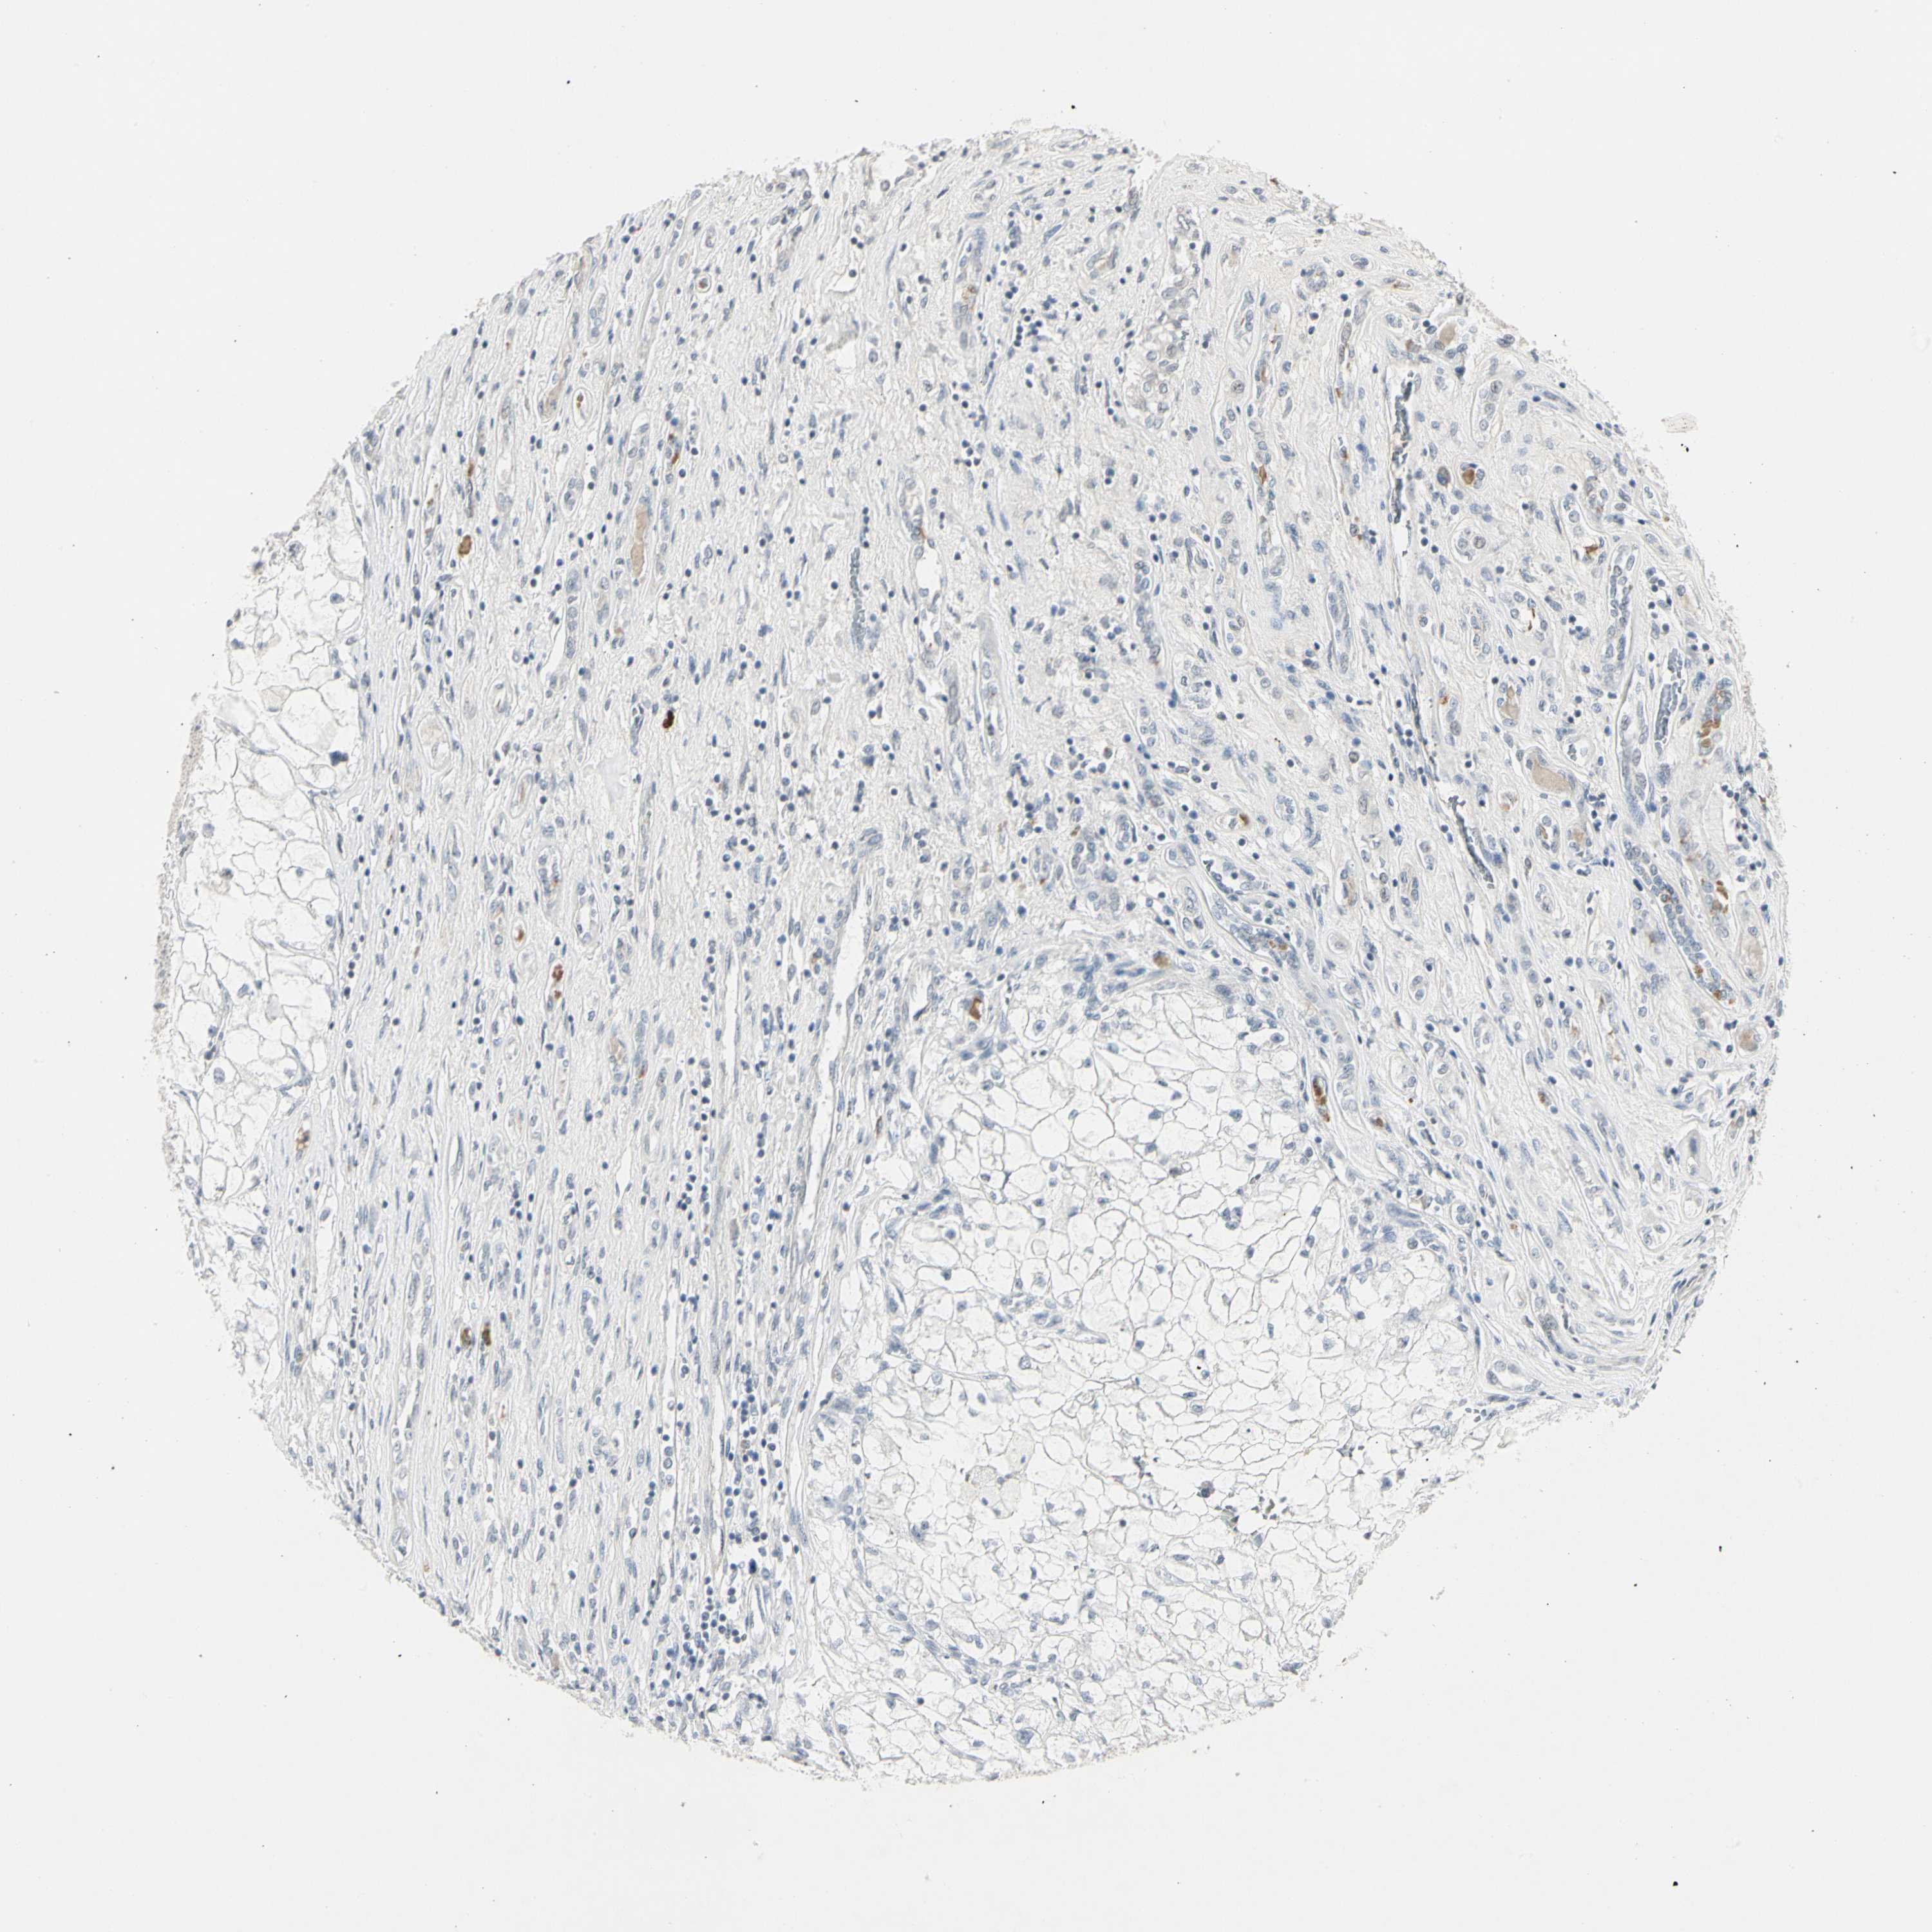

CANCER RENAL CANCER Show tissue menu

KICH TCGA KIRC TCGA KIRC VALIDATION KIRP TCGA PROTEIN RCC CPTAC PROTEIN EXPRESSION